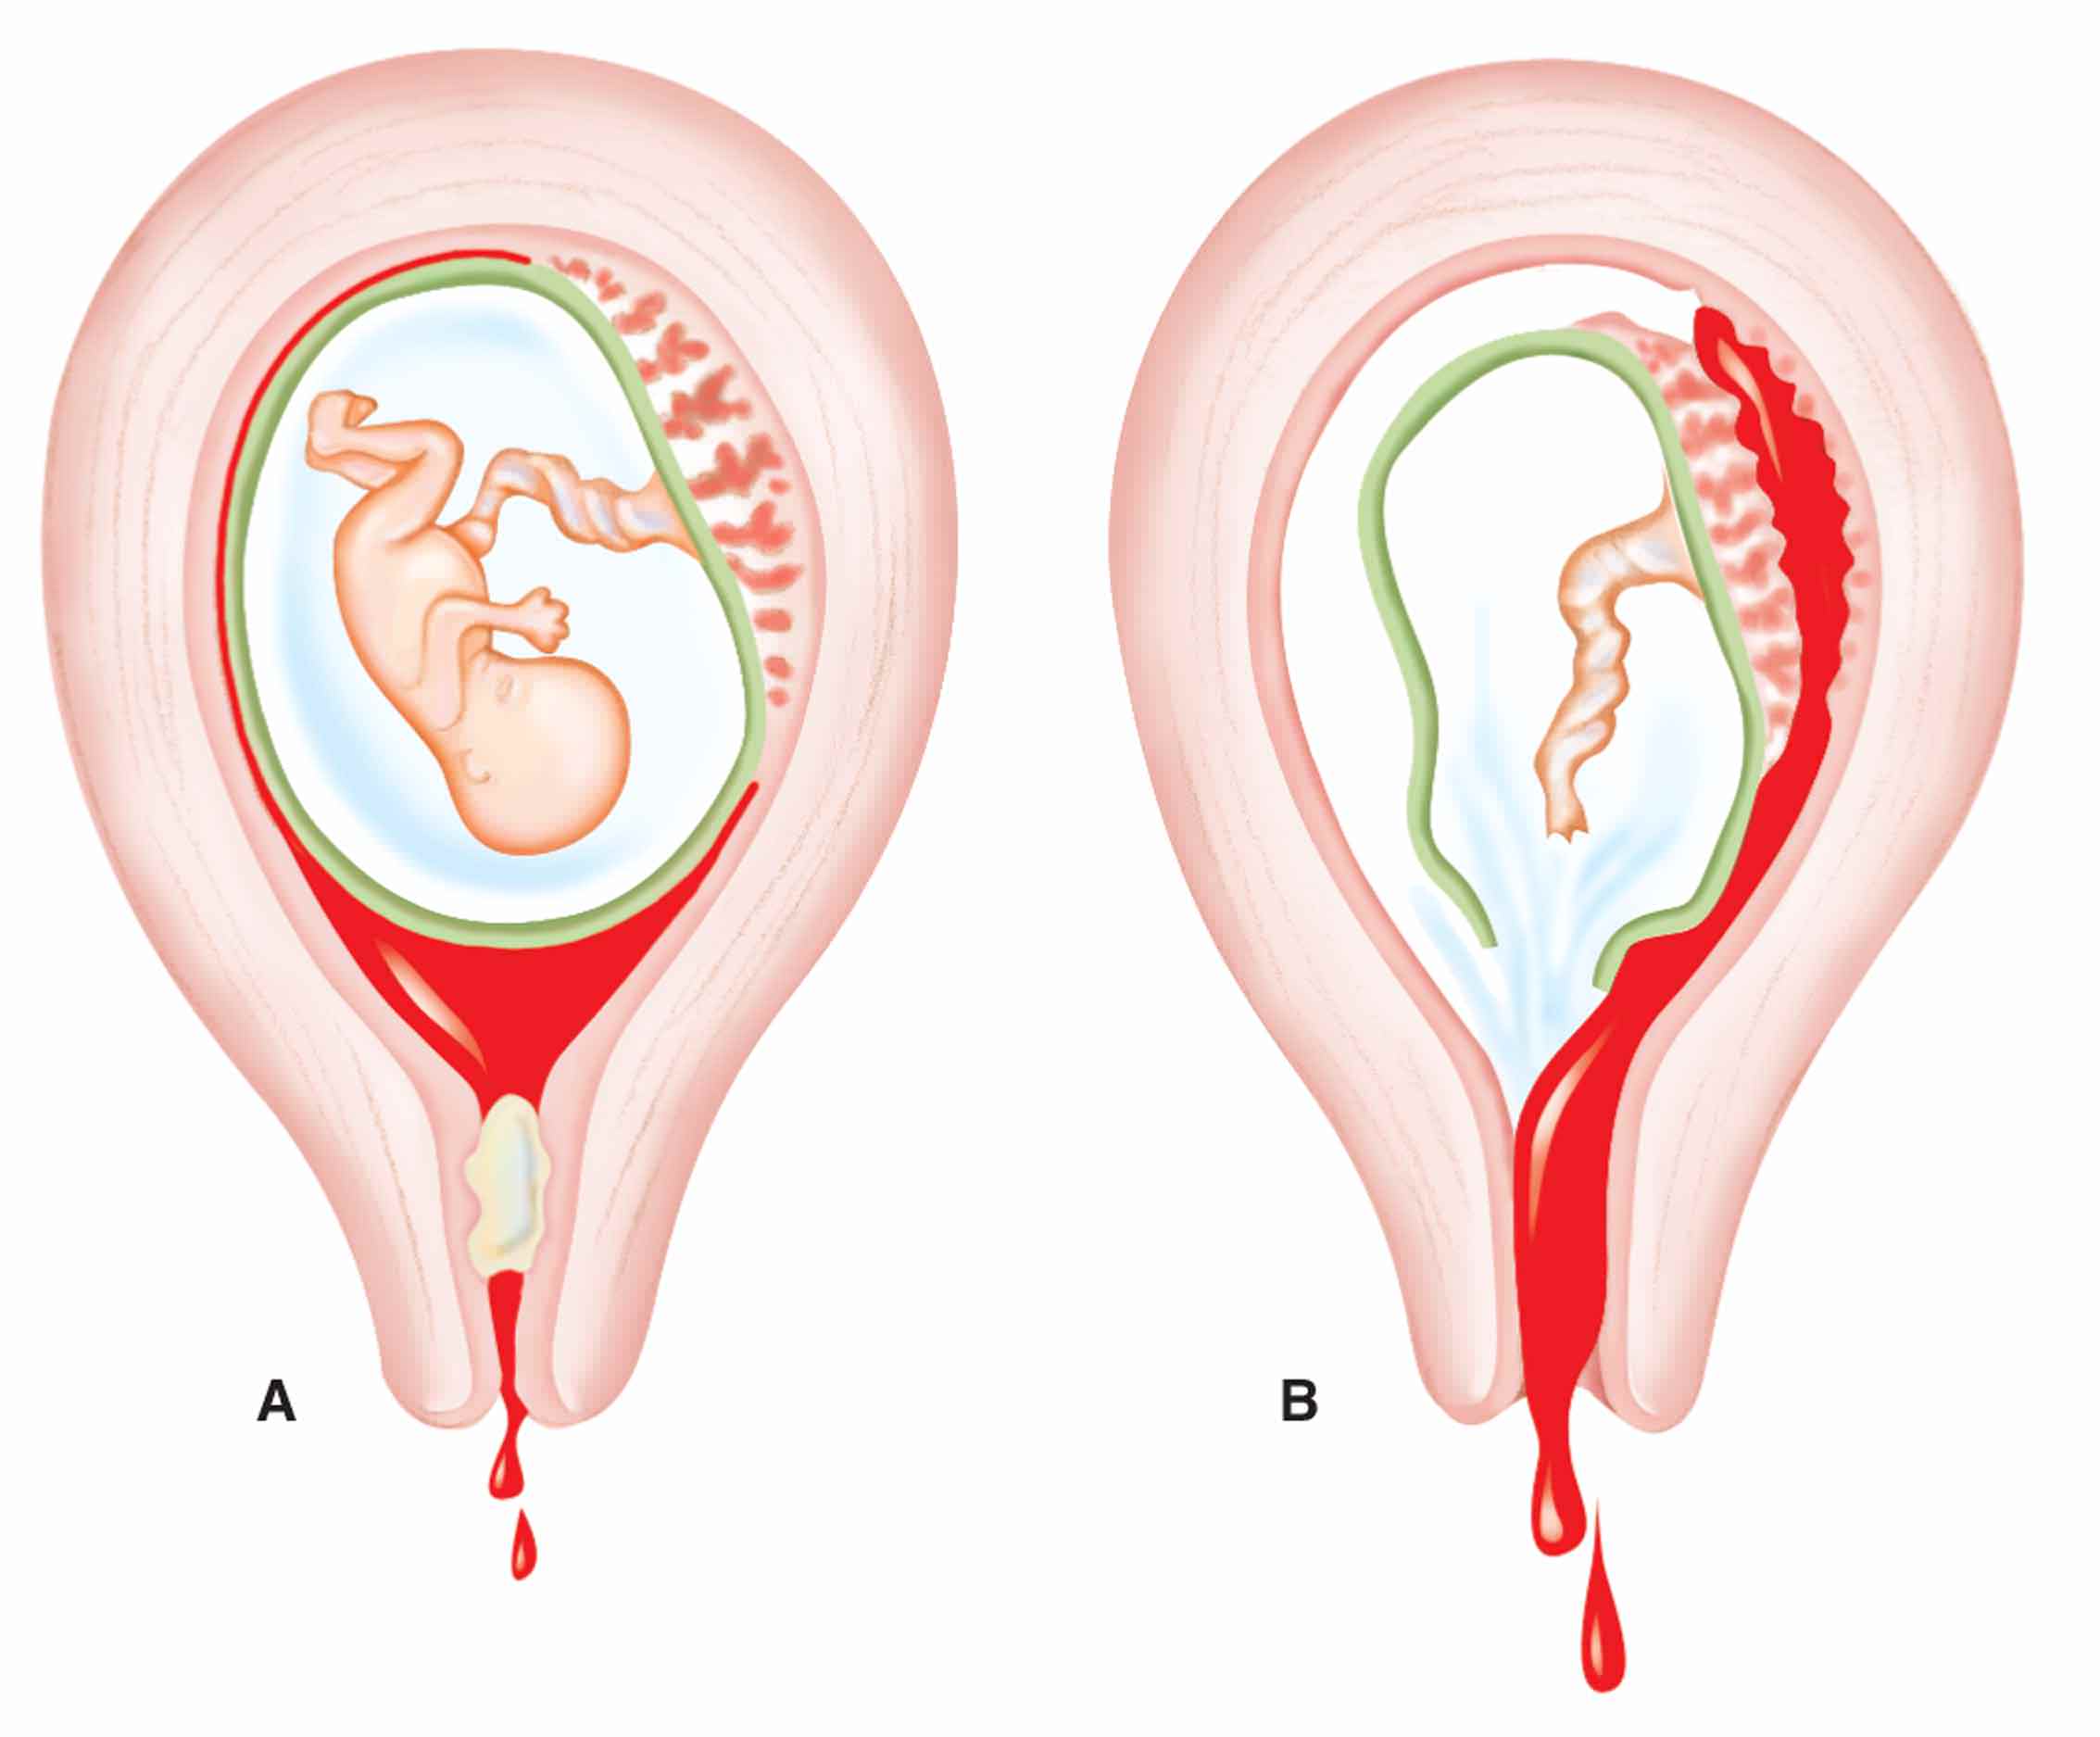

Анатомия женского организма: строение и функции матки

Раздел: Фотопуть к знанию